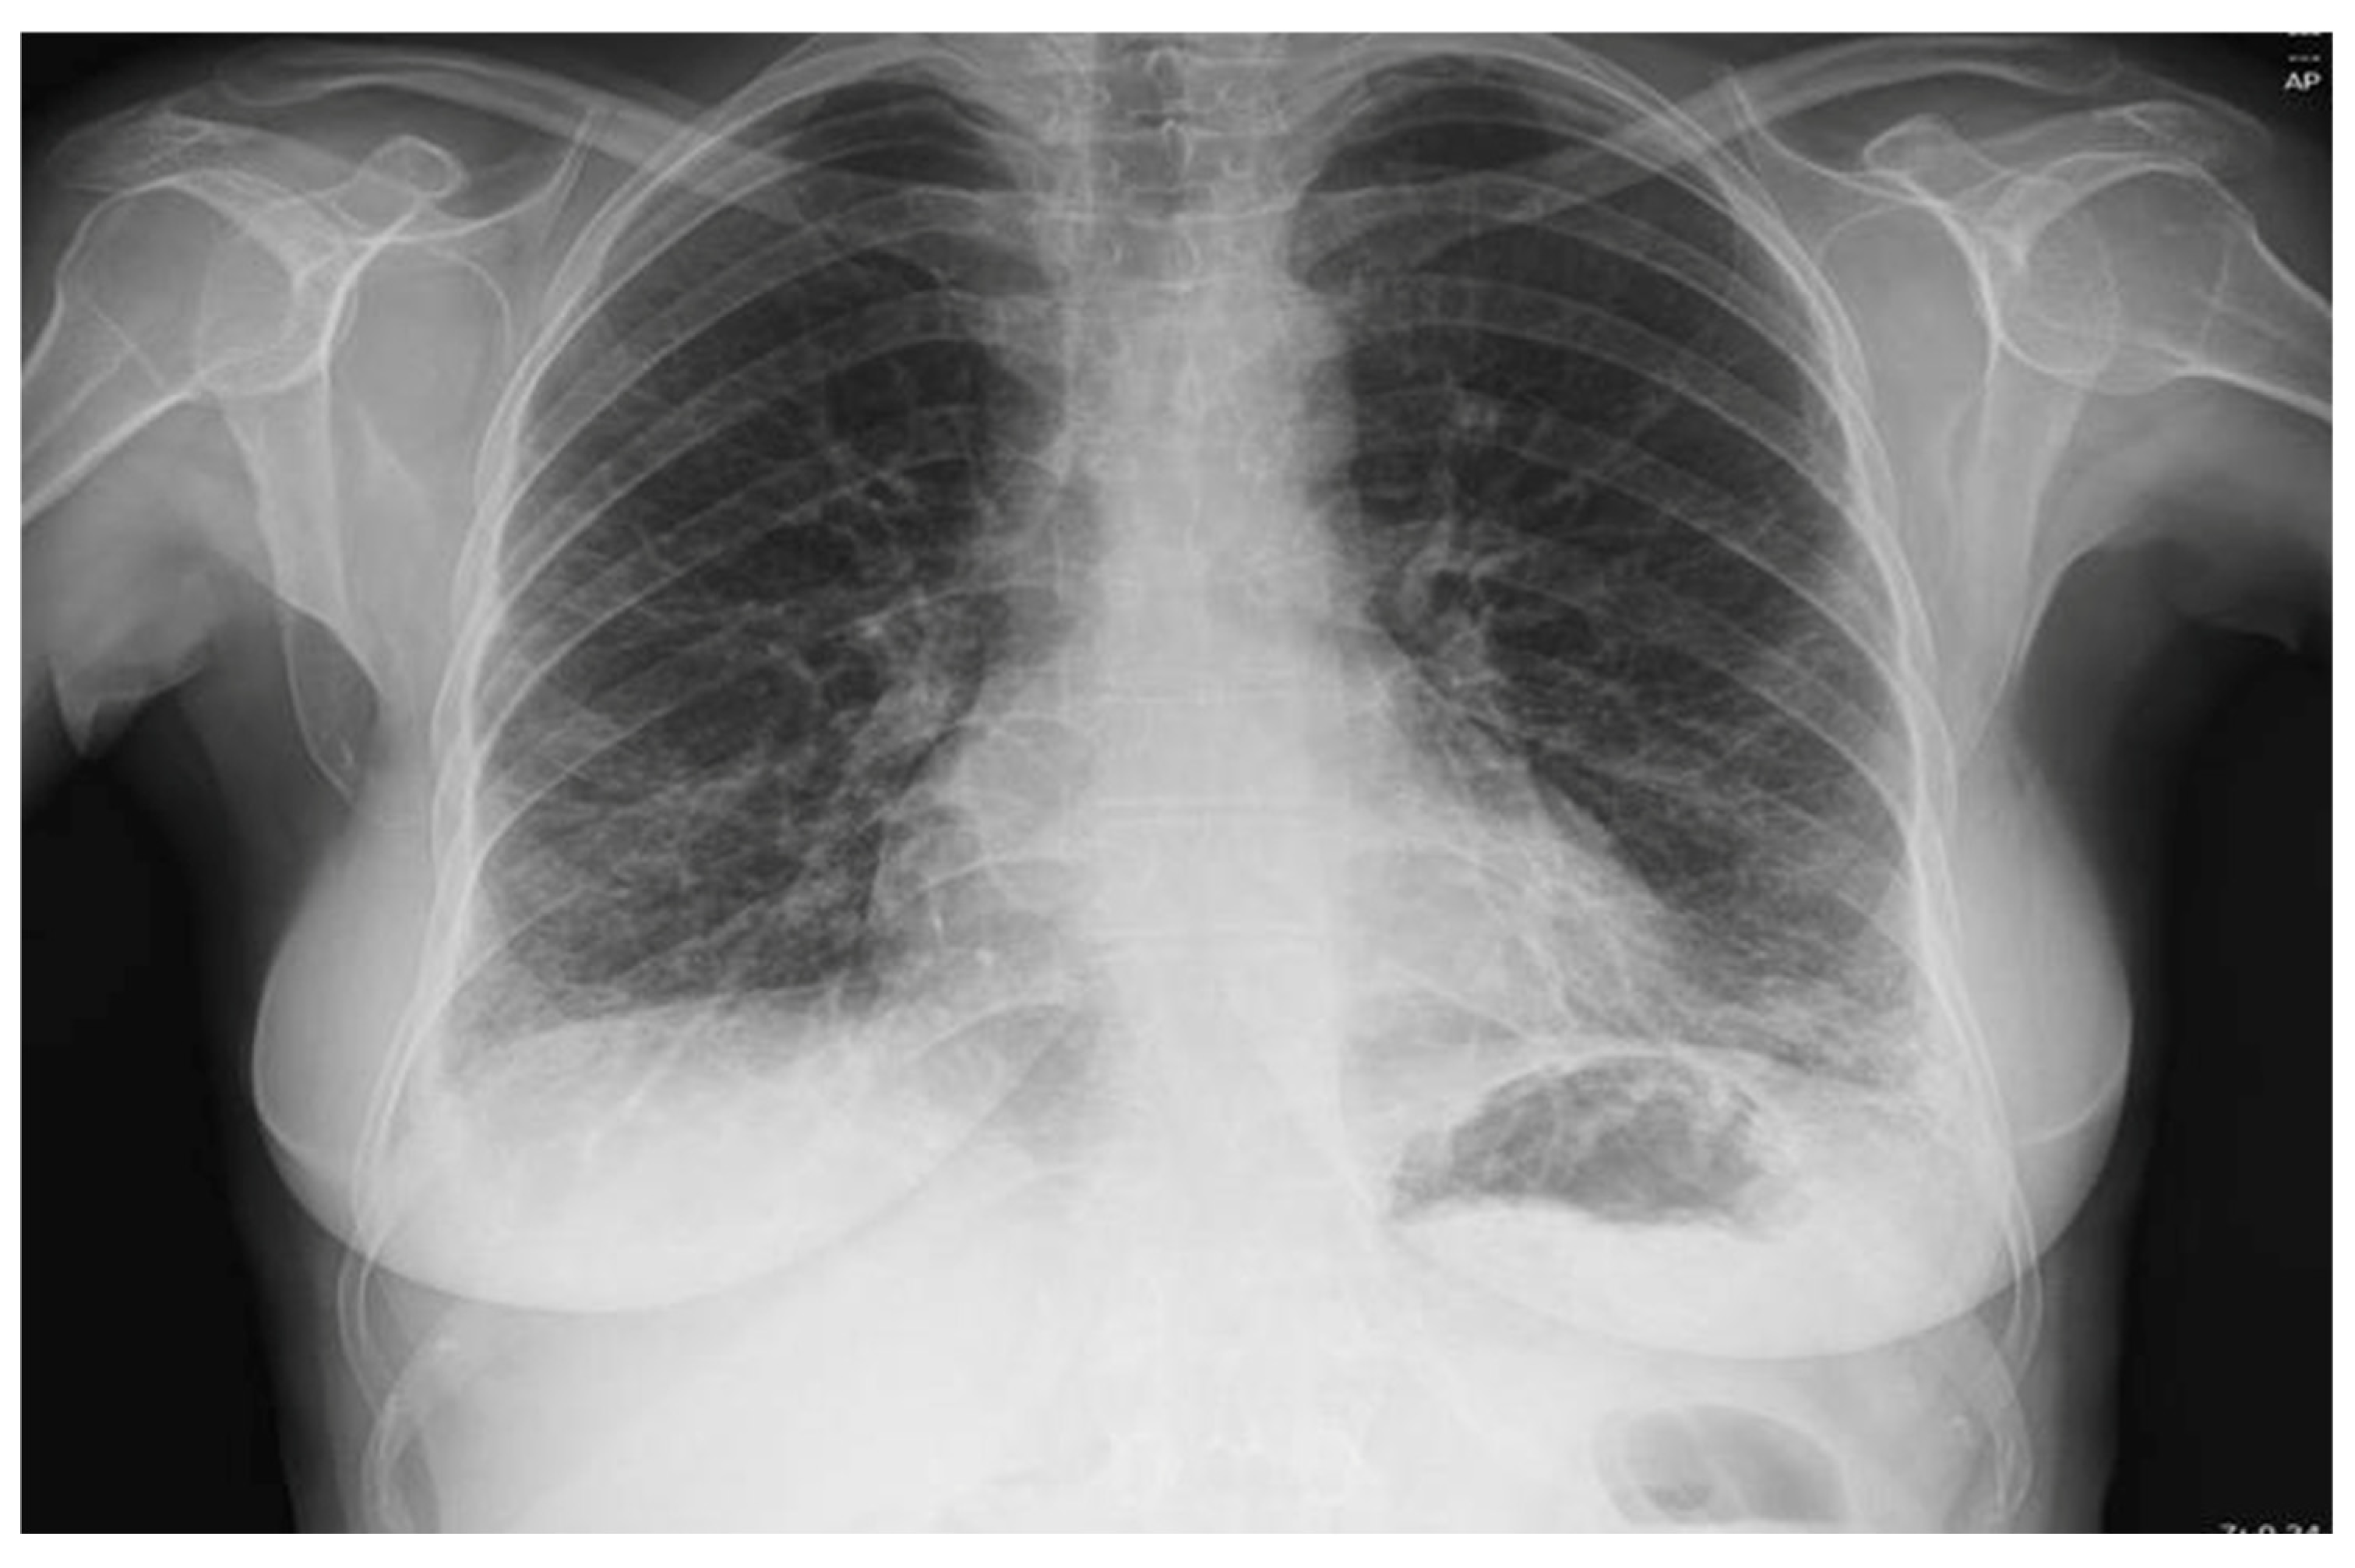

2. Case Presentation